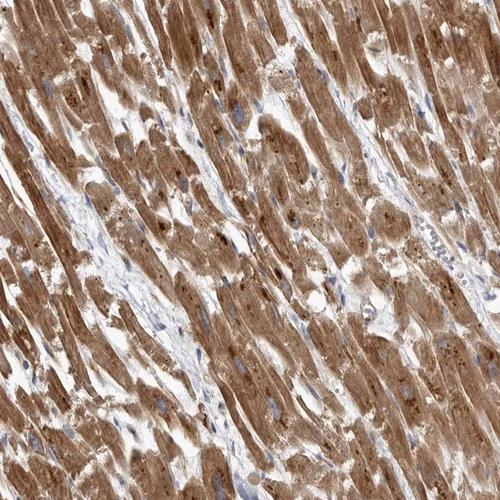

Immunohistochemical staining of human heart muscle shows strong cytoplasmic positivity in myocytes.